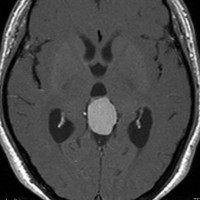

30代の女性に発生した髄膜腫です,一見すると松果体細胞腫と見分けはつきません。右の画像に見られるように典型的な中脳水道狭窄を生じていました。

軽度の閉塞性水頭症もありますが,頭痛も無く無症状なので経過を観察しました。髄膜腫だと診断できるのは,右の画像で見られるようにガレン大静脈が右側に偏っているからです。松果体細胞腫の場合は,ガレン大静脈は上方に変位します。

1年間経過観察したら水頭症が進行して脳室が拡大,腫瘍のサイズも大きくなりました。右側の画像で見られるようにガレン大静脈の左側のテントの下面から発生した髄膜腫でした。

左は手術直後の画像です,手術は左側のテント下面を見るために,後頭部経テント法 OTA occipital transtentorial approach で,小脳テントの左側を切断して腫瘍を全摘出しました。右側は6年後の画像ですが,腫瘍再発はありません。